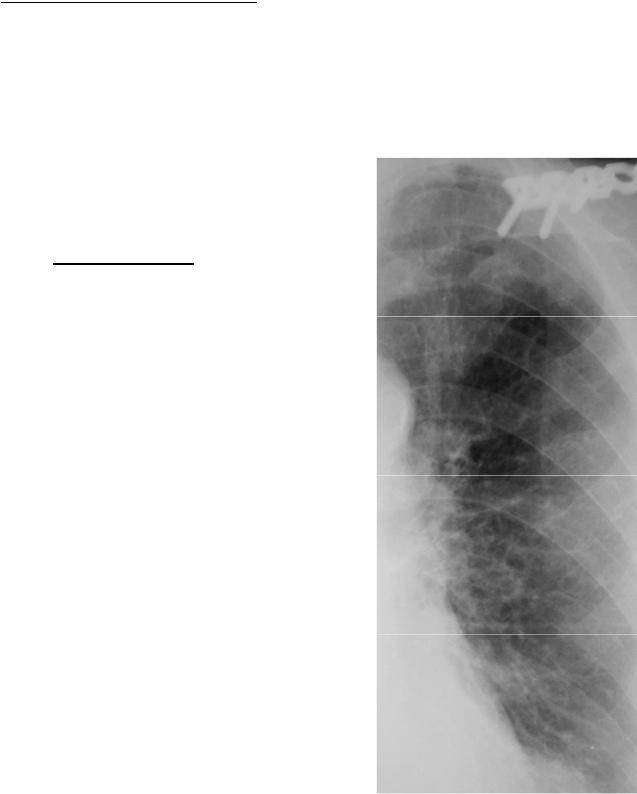

Фотографии, демонстрирующие обнаруженное усиление легочного рисунка

Раздел: Фотодневник открытий